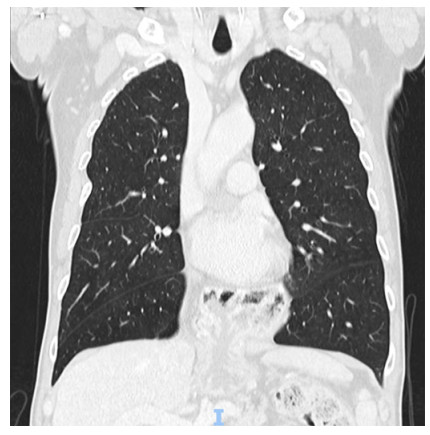

Abstract: Hiatal hernia is a rare postoperative complication of esophagectomy in the treatment of esophageal cancer. Although rare, its incidence increased after the establishment of minimally invasive surgical techniques. The patient is usually oligosymptomatic, and the diagnosis is made in the late postoperative period, during outpatient follow-up. The initial presentation of hiatus hernia with hemodynamic instability is a rare condition that has never been described in the literature before. In the following report, we address the clinical picture, diagnosis, and treatment for this condition, discussing the main nuances of the literature.